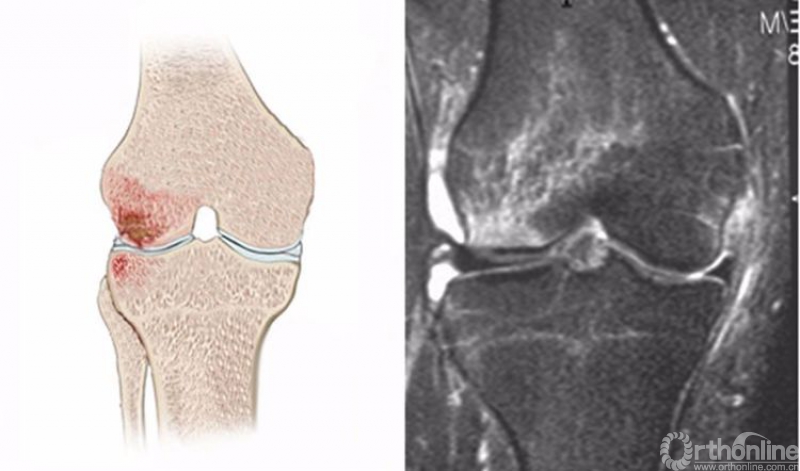

5.髌骨脱位(patellar dislocation)

髌骨脱位是一种常见的损伤,其损伤是短暂性的,病人不一定意识到,而在体检时由于肿胀和疼痛而影响检查,因此有50%-70%的患者在初次就诊时不能获得诊断。

髌骨脱位是髌骨内侧与股骨外髁外侧壁发生撞击,在MRI上主要表现为髌骨内侧及股骨外髁外侧壁的骨髓水肿,T2WI及STIR像呈高信号改变。可合并内侧髌股副韧带撕裂、髌骨及其股骨外髁的骨软骨损伤。